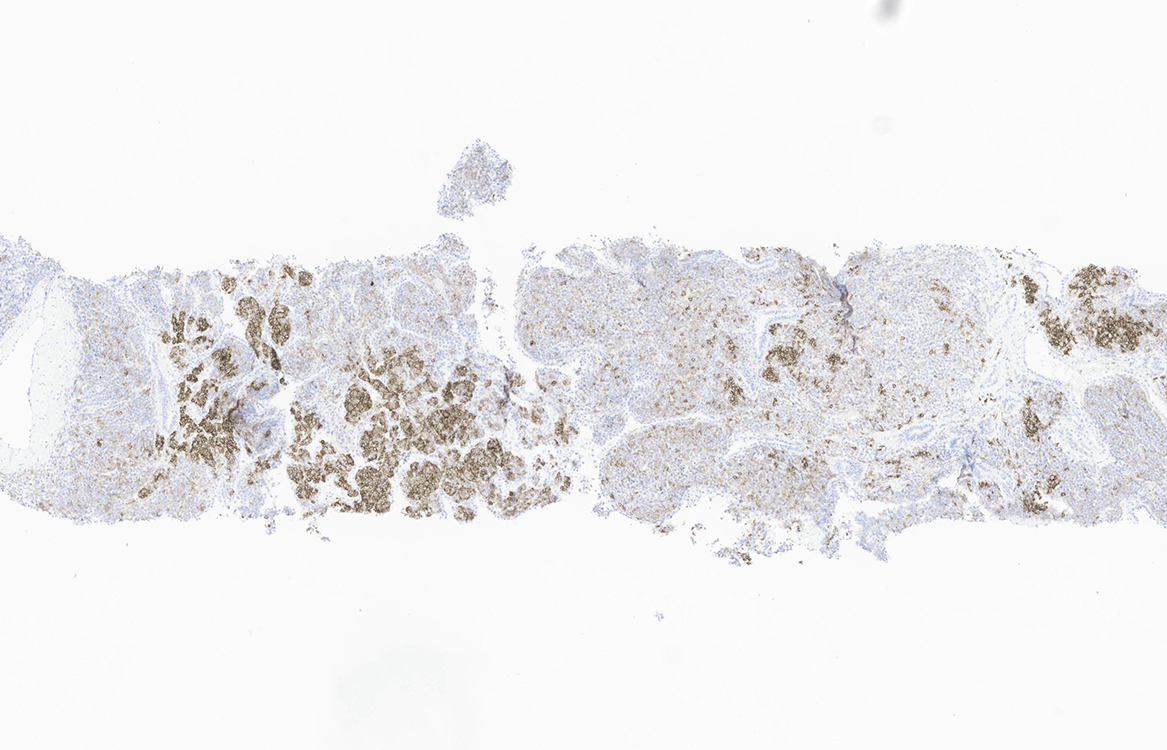

Figure 6 (CD56)